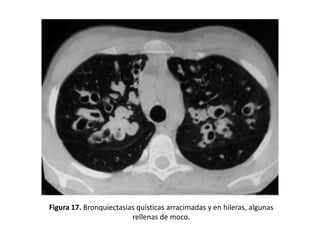

• Impactos mucoides:

– Pueden aparecer como opacidades lobuladas, en dedo de guante,

ramificadas (en forma de Y o de V) o redondeadas (cuando el plano de

corte es transversal al impacto mucoso se pueden confundir con una

arteria). (Figura 16 y 17).

Figura 17. Bronquiectasias quísticas arracimadas y en hileras, algunas

rellenas de moco.

Signos indirectos • Engrosamientode la pared bronquial: – Mayor de 50% del diámetro de la arteria adyacente. – Es un hallazgo muy frecuente pero inespecífico ya que puede aparecer en otras patologías. – Se debe medir mediante el índice de luz bronquial, que es el cociente entre el diámetro interno y externo del bronquio (Figura 15). • Impactos mucoides: – Imágenes tubulares con densidad de partes blandas que representan el bronquio dilatado y repleto de moco: “bronquio en positivo”, o con niveles hidroaéreos. – Pueden aparecer como opacidades lobuladas, en dedo de guante, ramificadas (en forma de Y o de V) o redondeadas (cuando el plano de corte es transversal al impacto mucoso se pueden confundir con una arteria). (Figura 16 y 17).

Figura 17. Bronquiectasiasquísticas arracimadas y en hileras, algunas rellenas de moco.